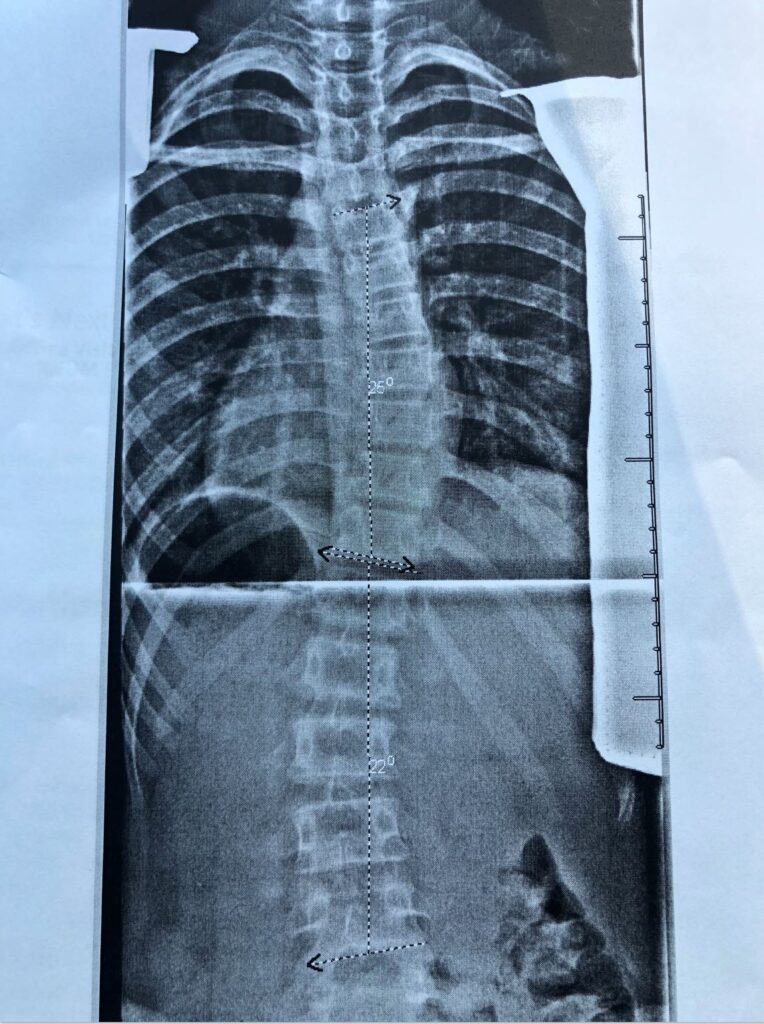

Three years later, I am still struck by my spine’s curvature. But these reminders have become more than just discomfort, they now serve as lessons in appreciating all that I take for granted. Accepting my diagnosis was the first step in realizing my potential for growth and development. Only when I decided to pick up my feet instead of wallowing in my loneliness was I able to transcend my physical limitation, my “can’t.” I began to move forward focusing not on what my brace had limited me to, but on all that I could do, leaning on my family and those surrounding me as my new pillar of strength. With their encouragement, I began to stretch my arms out to those around me, recognizing a community of younger peers who, like me, were braced and twisted. I felt compelled to make it known to them that they are, in no way, alone in this journey. As I aspire to build this system of support for others by sharing my story, I hope to become a resource for them, demonstrating that there is indeed a light at the end of the tunnel.